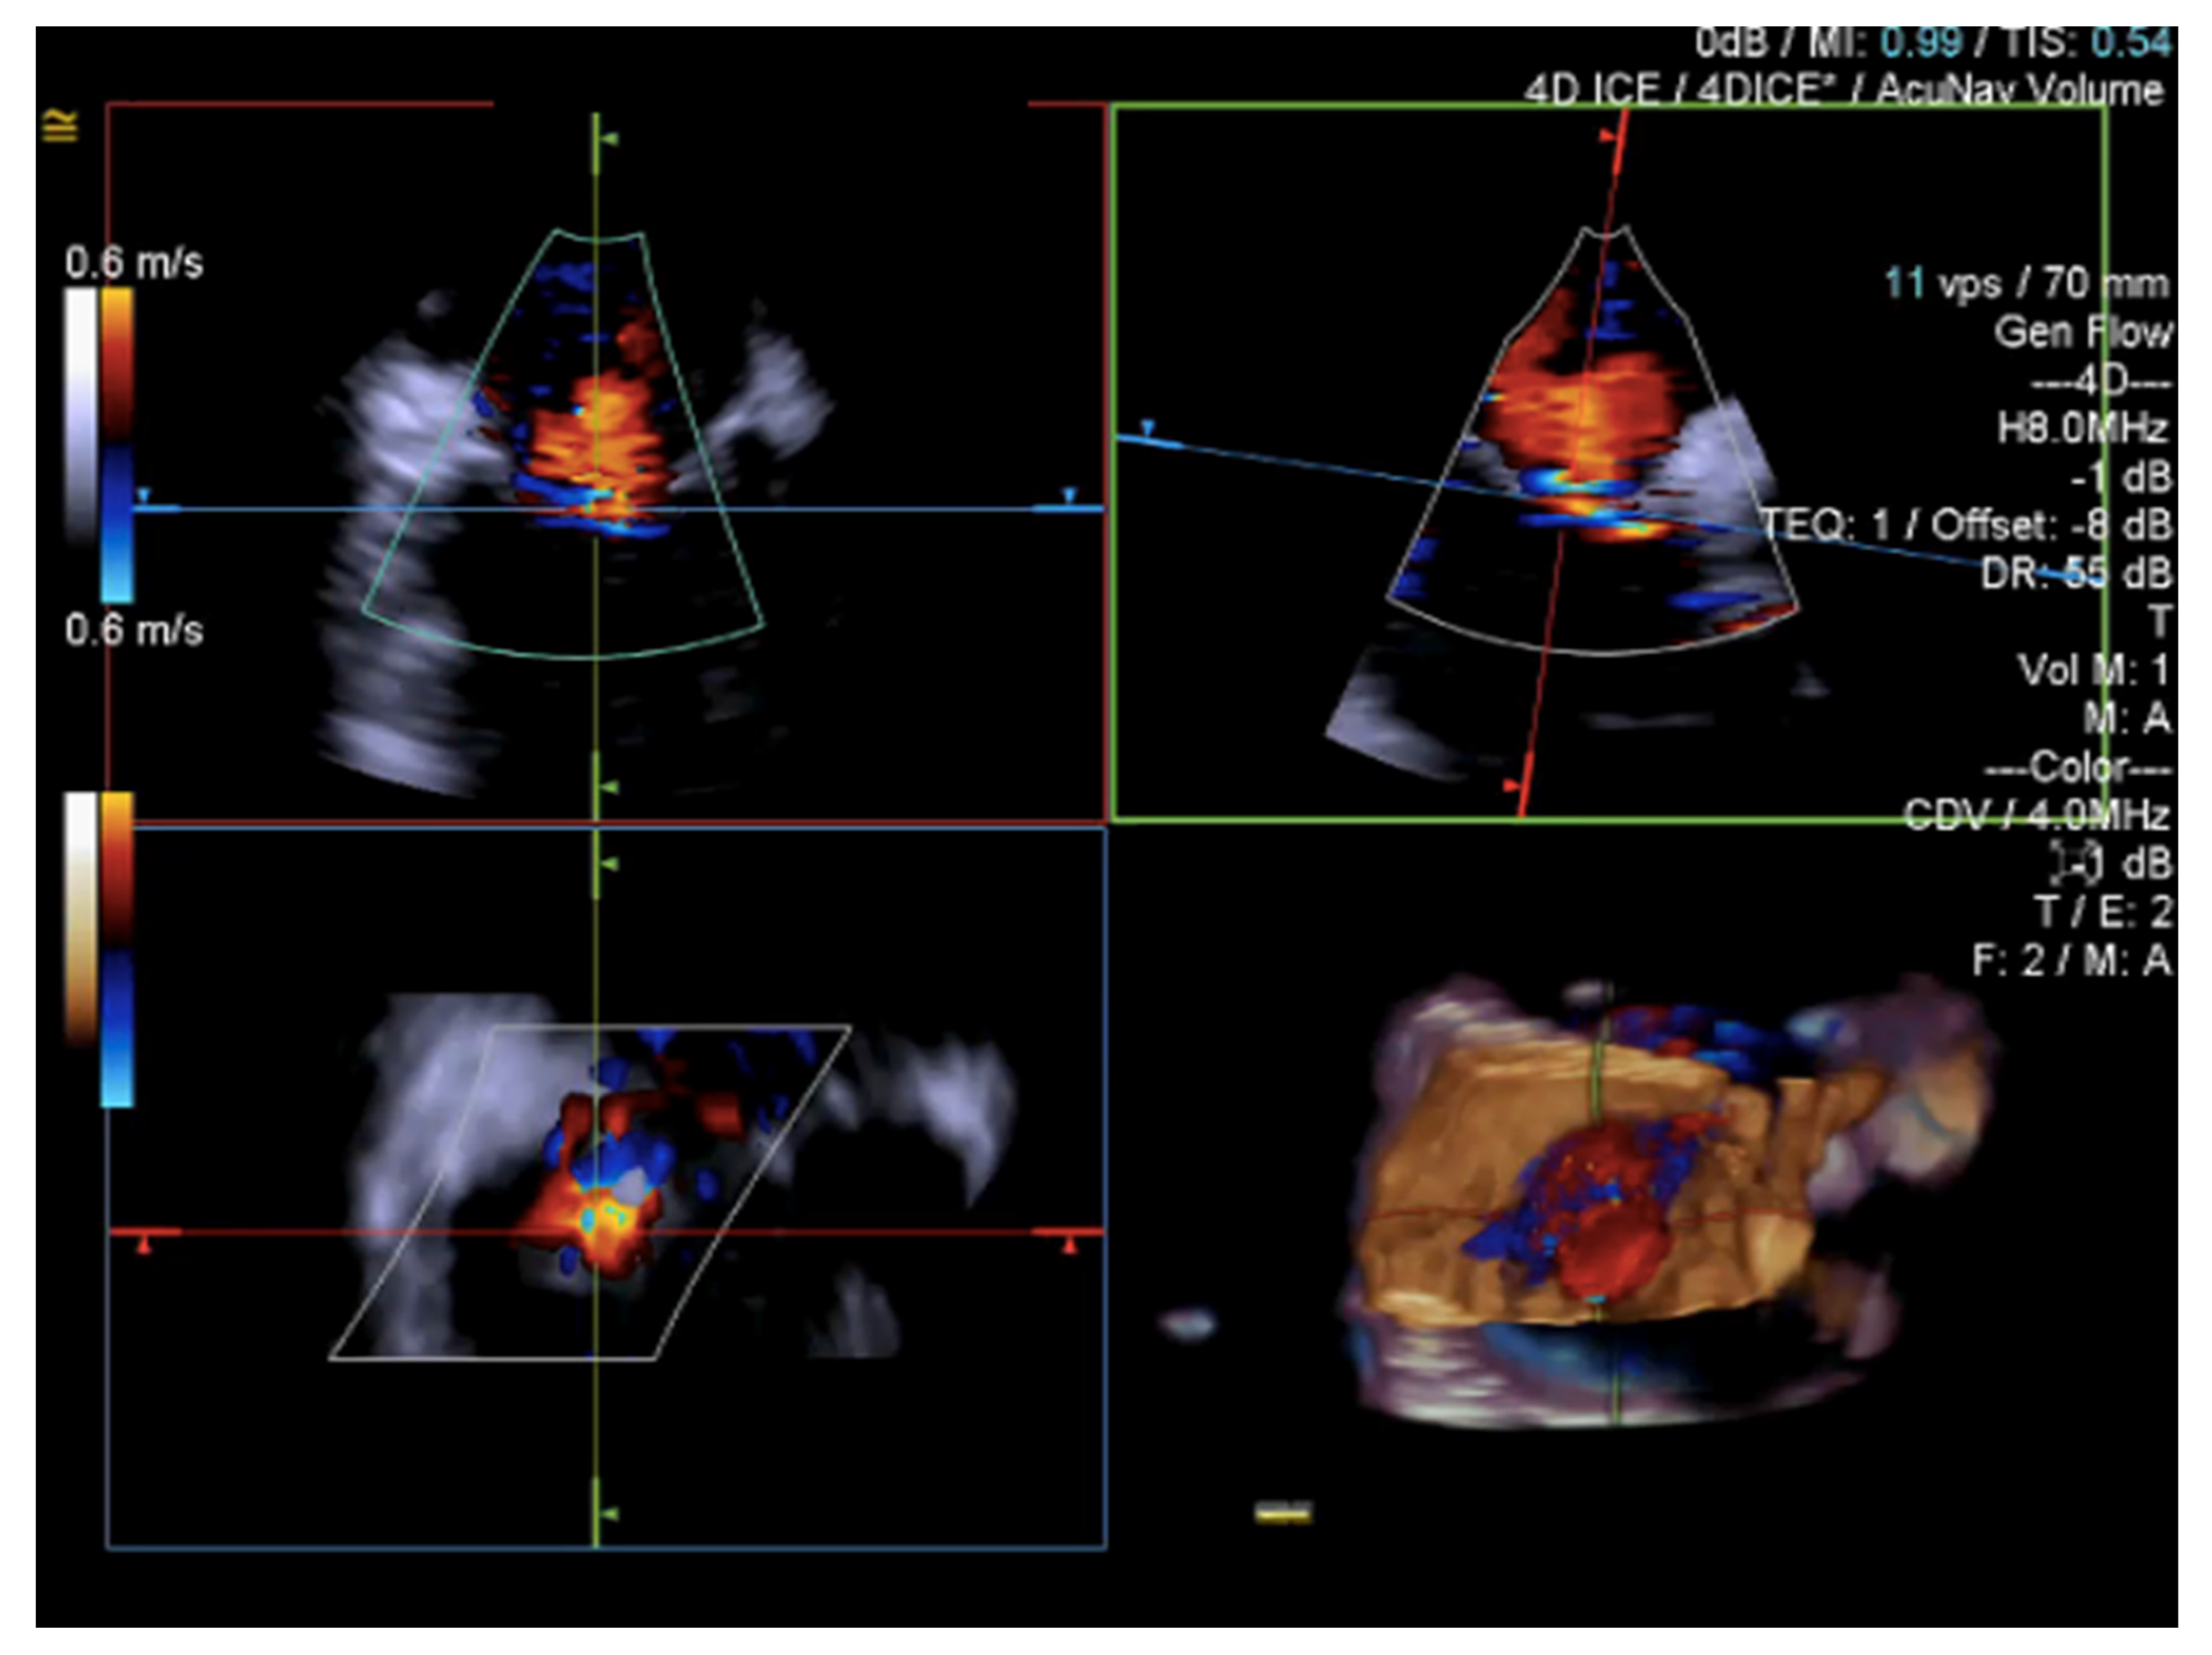

- Tang, G.H.; Yakubov, S.J.; Soto, C.E.S. 4-Dimensional Intracardiac Echocardiography in Transcatheter Tricuspid Valve Repair with the MitraClip System. JACC Cardiovasc. Imaging 2020, 13, 1591–1600. [Google Scholar] [CrossRef]

- Silvestry, F.E.; Kadakia, M.B.; Willhide, J.; Herrmann, H.C. Initial experience with a novel real-time three-dimensional intracardiac ultrasound system to guide percutaneous cardiac structural interventions: A phase 1 feasibility study of volume intracardiac echocardiography in the assessment of patients with structural heart disease undergoing percutaneous transcatheter therapy. J. Am. Soc. Echocardiogr. 2014, 27, 978–983. [Google Scholar] [CrossRef]